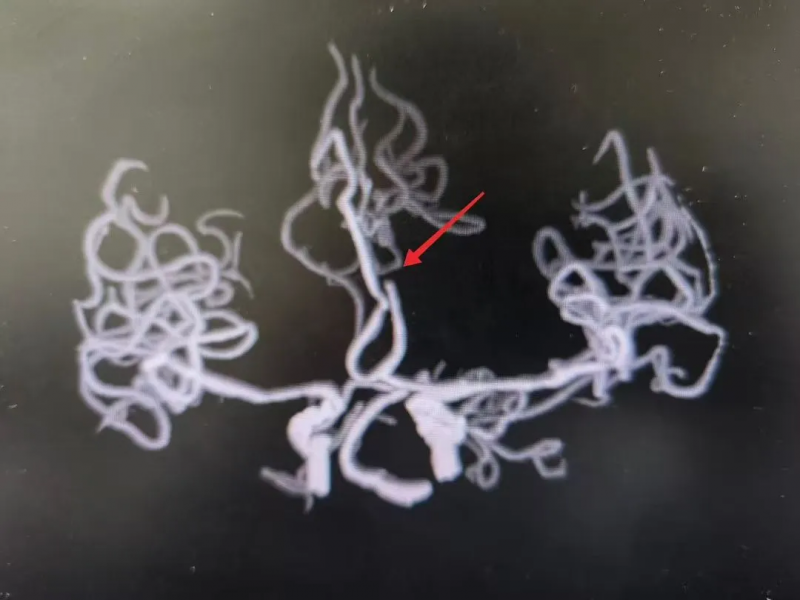

“大血管闭塞,必须立即进行血管内取栓治疗!”徐爱元副主任医师根据影像学结果和迅速恶化的病情,果断判断患者为左侧大脑前动脉闭塞。与家属充分沟通并取得同意后,一场与时间赛跑的手术即刻展开。

在医院麻醉科、介入室、内一科团队的紧密配合下,患者被迅速送入介入室。由于患者血管有变异,且迂曲,考虑在大脑前动脉病变,需要在全身麻醉下,由经验丰富的内一科团队施行“全脑血管造影术+血管内取栓术”。凭借精湛的技术,成功将堵塞血管的血栓取出,恢复了大脑前动脉的血流。手术取得了立竿见影的效果,术后,患者生命体征平稳,很快从麻醉中苏醒。